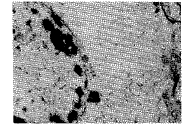

脑损伤组脑组织细胞浆高度水肿,空泡变性显著,细胞膜断裂,细胞器少见,核膜不连续,核碎裂、靠边(见图1)。毛细血管基底膜破坏。脑损伤+PNS组脑组织,核膜完整,核仁清楚,胞浆无明显水肿(见图2),毛细血管基底膜完整。

Fig 1 Neuron cellular edema and nucleolar margination in

brain injury group TEM×5 000

图1 脑损伤组,神经元水肿,核仁靠边

Fig 2 Neuron cellular edema disappearance in brain

injury+PNS group TEM×5 000

图2 脑损伤+PNS组,神经元水肿消失,核膜完整